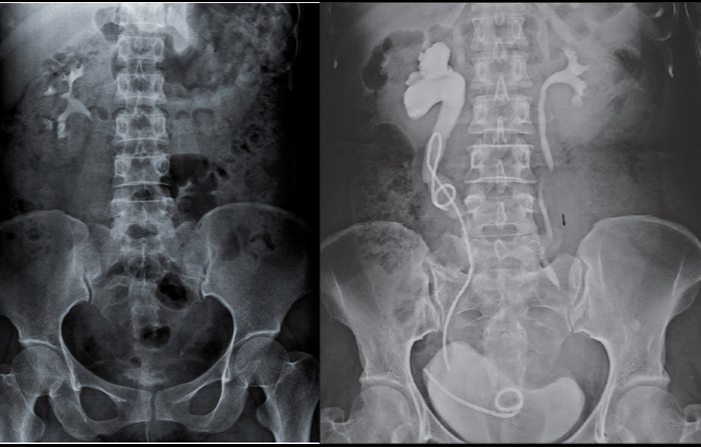

Chụp X quang hệ tiết niệu là một phương pháp sử dụng hình ảnh để chẩn đoán, đánh giá các cơ quan và cấu trúc trong hệ tiết niệu của cơ thể bao gồm thận, bàng quang và ống niệu.

Phương pháp này sử dụng tia X để tạo ra hình ảnh hai chiều của các cơ quan, cho phép bác sĩ đánh giá kích thước, hình dạng, vị trí và chức năng của chúng.

Quá trình chụp X quang hệ tiết niệu thường bao gồm tiến hành chụp X quang của thận, bàng quang và ống niệu. Bệnh nhân thường được yêu cầu thay đổi vị trí để tạo ra những góc chụp khác nhau với các hình ảnh chi tiết để bác sĩ có thể xem xét từng khía cạnh của hệ tiết niệu.